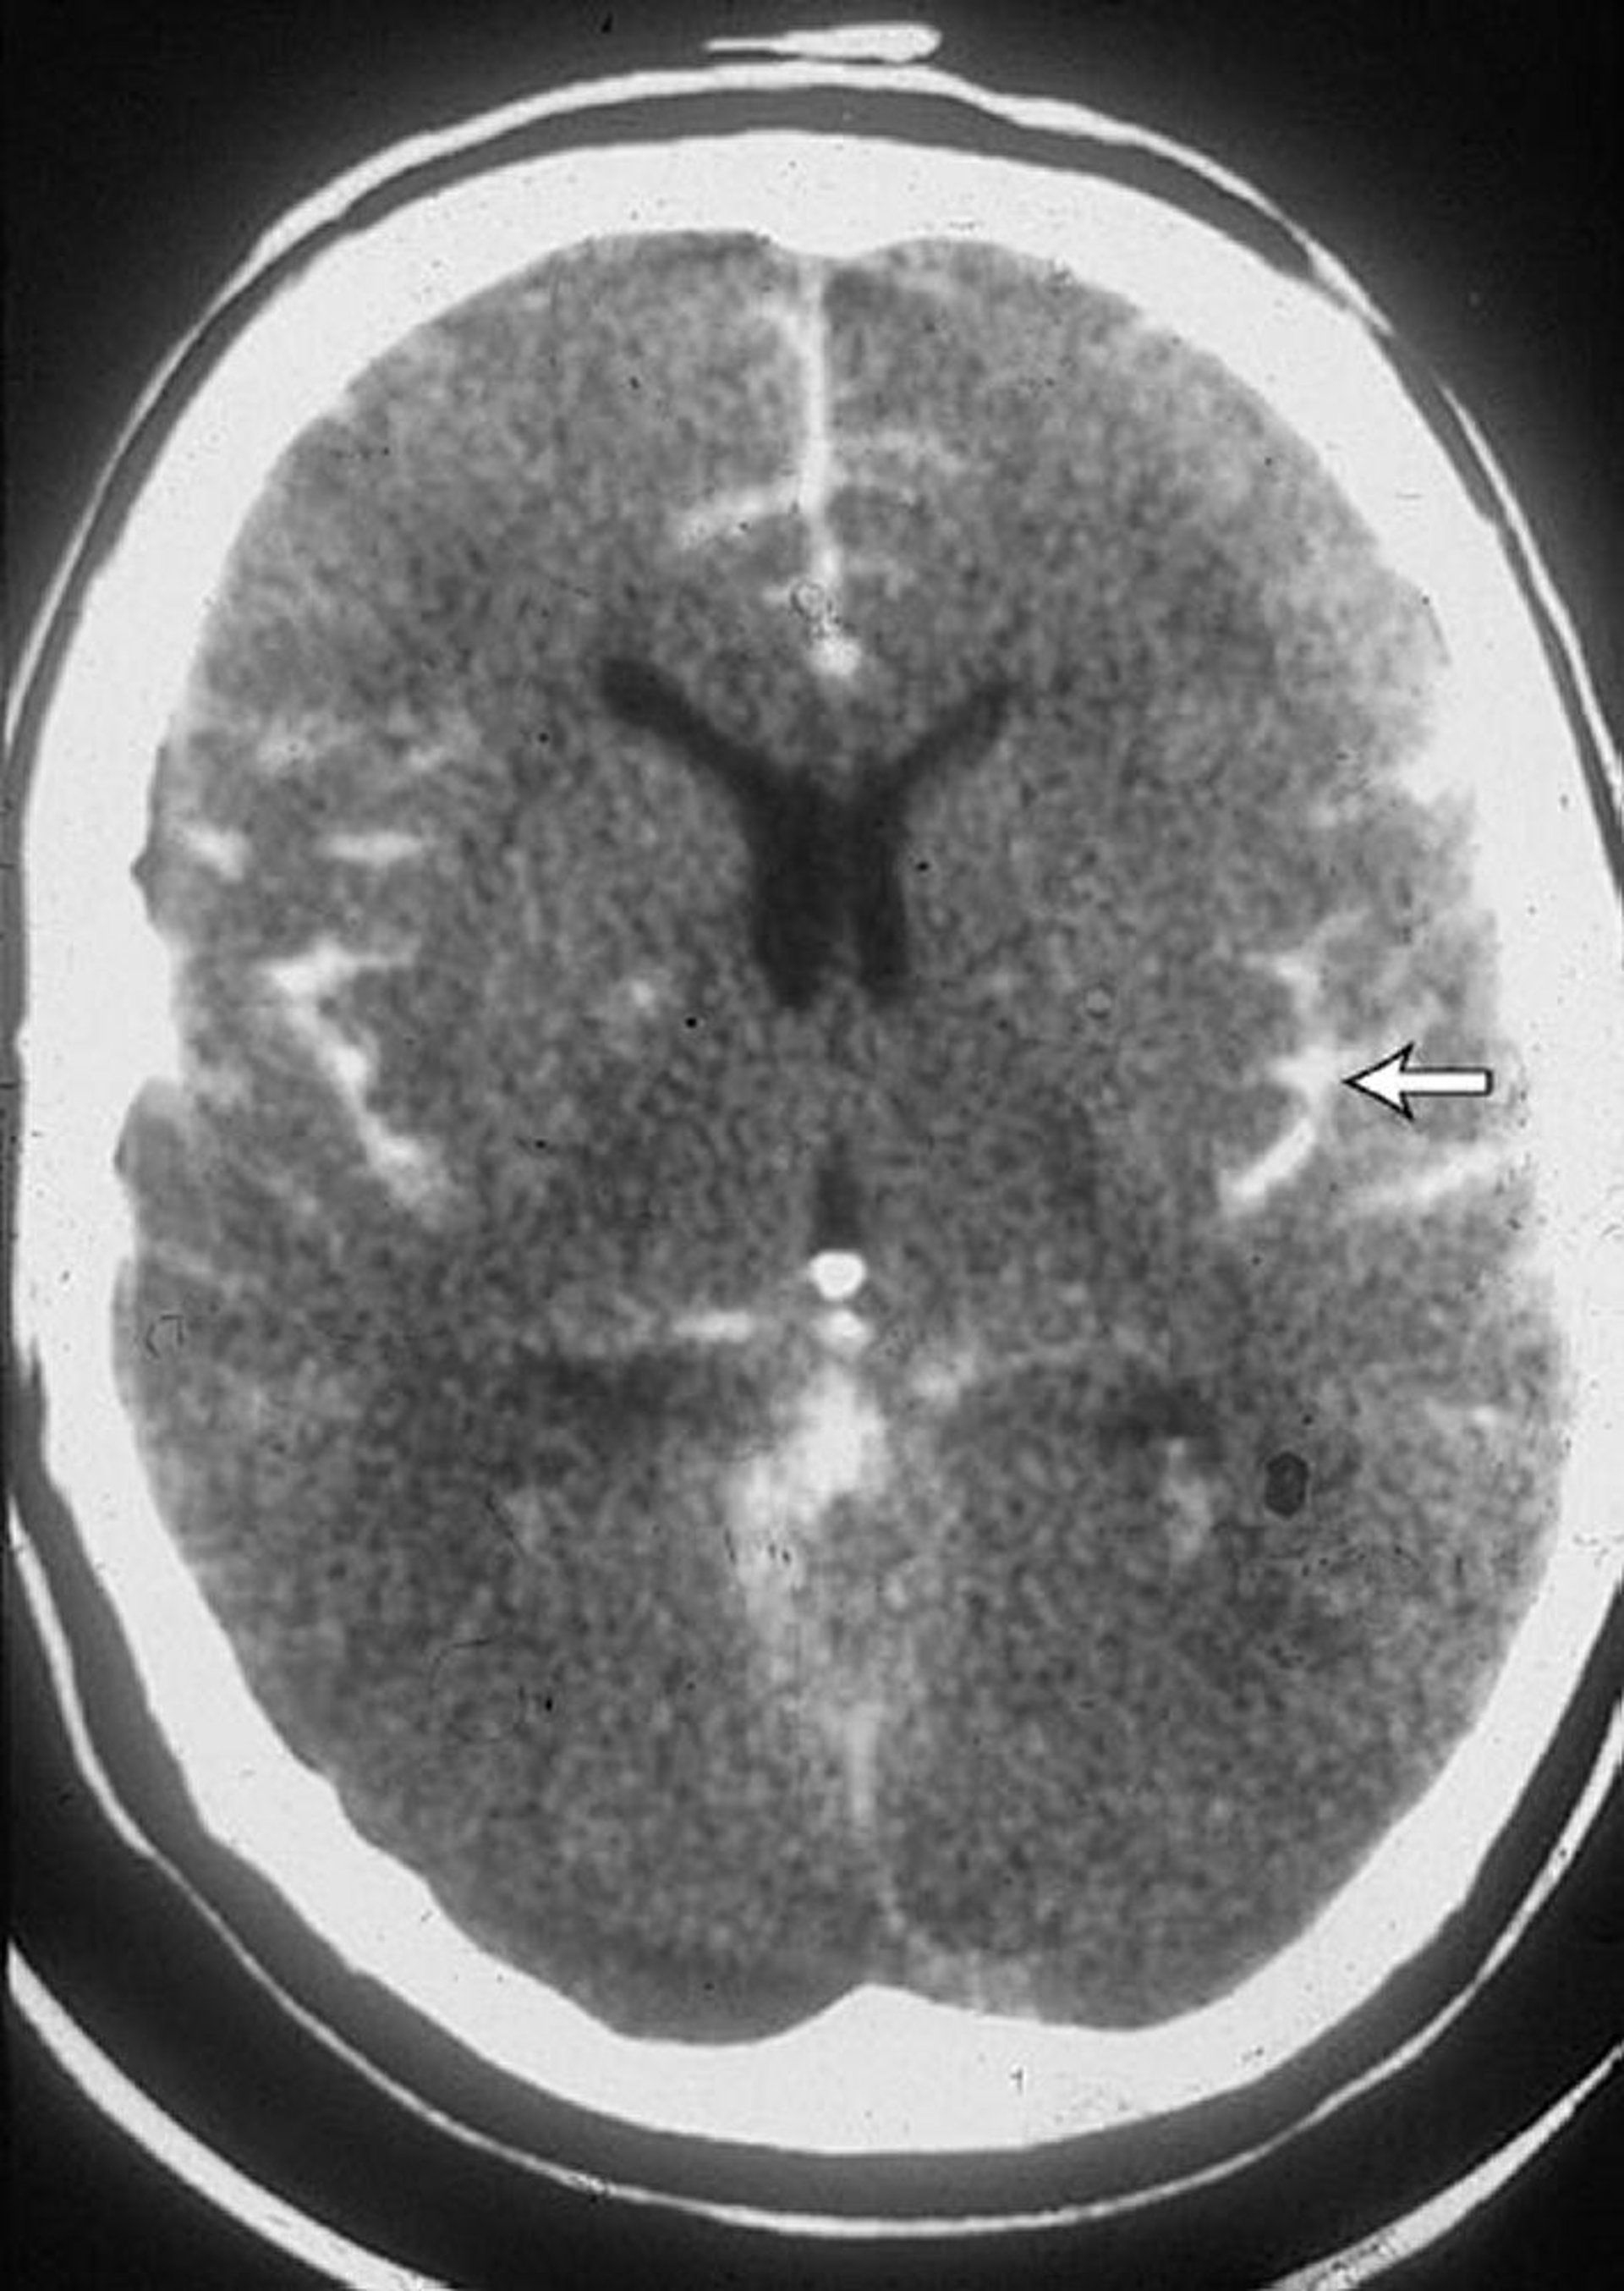

This CT scan in a patient with a subarachnoid hemorrhage shows blood in the sulci (arrow). Blood is often also seen in the ventricles.

By permission of the publisher. From Lenaerts M, Couch J. In Atlas of Clinical Neurology. Edited by RN Rosenberg. Philadelphia, Current Medicine, 2002.